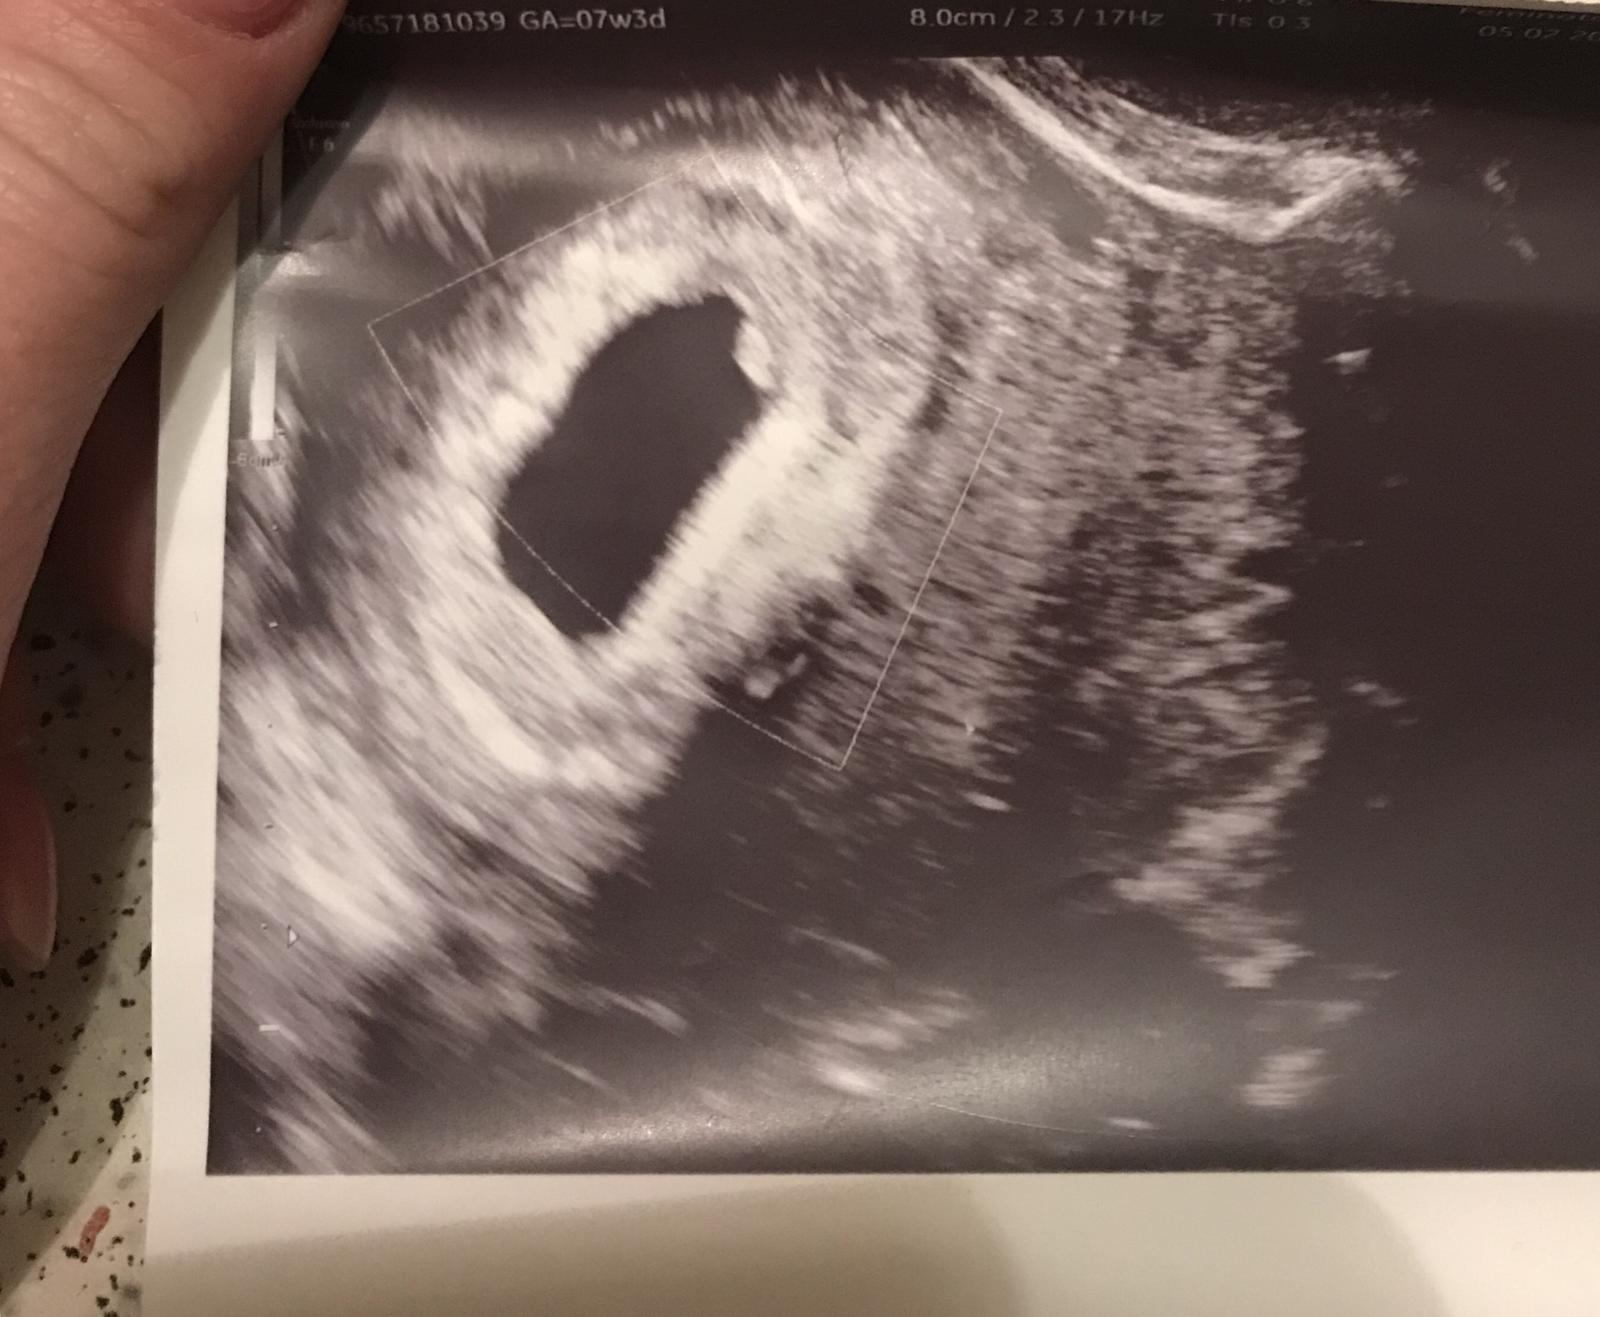

@loli9511 ja mam skusenost a to mam dve 🙂 ze ak ti digi ukazal 1-2 resp 2-3 tak je to naisto ze mas v sebe HCG..tie pruzkove su sice fajn ,ukazali ducha a bolo to tehu..ale ked naozaj chces byt ista tak digi a ten ti vysiel..neni o com 🙂..a ber to tak..ked je babo zdrave, silne udrzi sa a ked nie, odide..nic sa s tym neda robit...:( ale mne pri prvej pomohol duphaston..mozno ti ho aj sam doky pre istotu do toho 12tt da..je to len progesteron akoby taka poistka ked nefunguje dobre zlte teliesko..ja mam PCO a mam tento problem je to iba hormonalna vec takze mne Duphaston malu udrzal a teraz mi robi nervy :D